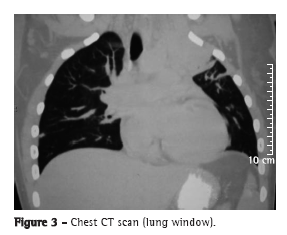

The patient was referred to the thoracic surgery department of our hospital for diagnostic investigation. Contrast-enhanced magnetic resonance imaging showed a mass with irregular borders, measuring 9.2 × 7.2 × 6.0 cm. The mass occupied the entire left upper lobe, invading the mediastinum and chest wall and involving the left common carotid artery, the left subclavian artery, and part of the aortic arch (Figure 1). A CT scan of the chest revealed invasion of the abovementioned structures and of the vertebral bodies, as well as the left supraclavicular fossa (Figures 2 and 3).

There are no radiological signs that are indicative of thoracic actinomycosis,(4) and chest X-ray findings can mimic a wide variety of diseases, including pulmonary infiltrate (suggestive of mild pneumonia) and micronodular infiltrate accompanied by pulmonary cavitation or large masses (suggestive of neoplasia), pleural effusion being common.(1,2,4,8,9) In advanced cases, a CT scan of the chest can reveal involvement of the chest wall, mediastinal involvement, and pleural involvement.(1,4,9) An image of diffuse involvement that crosses anatomical boundaries is highly suggestive of pulmonary actinomycosis.(4)